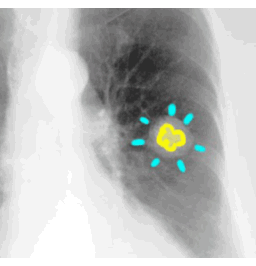

A

SHAPE - round

MARGIN - smooth

SIZE - 2.5 cm

DENSITY - central calcification

NOTE: any round lung opacity that is less than 3 cm in diameter can be called a 'NODULE'